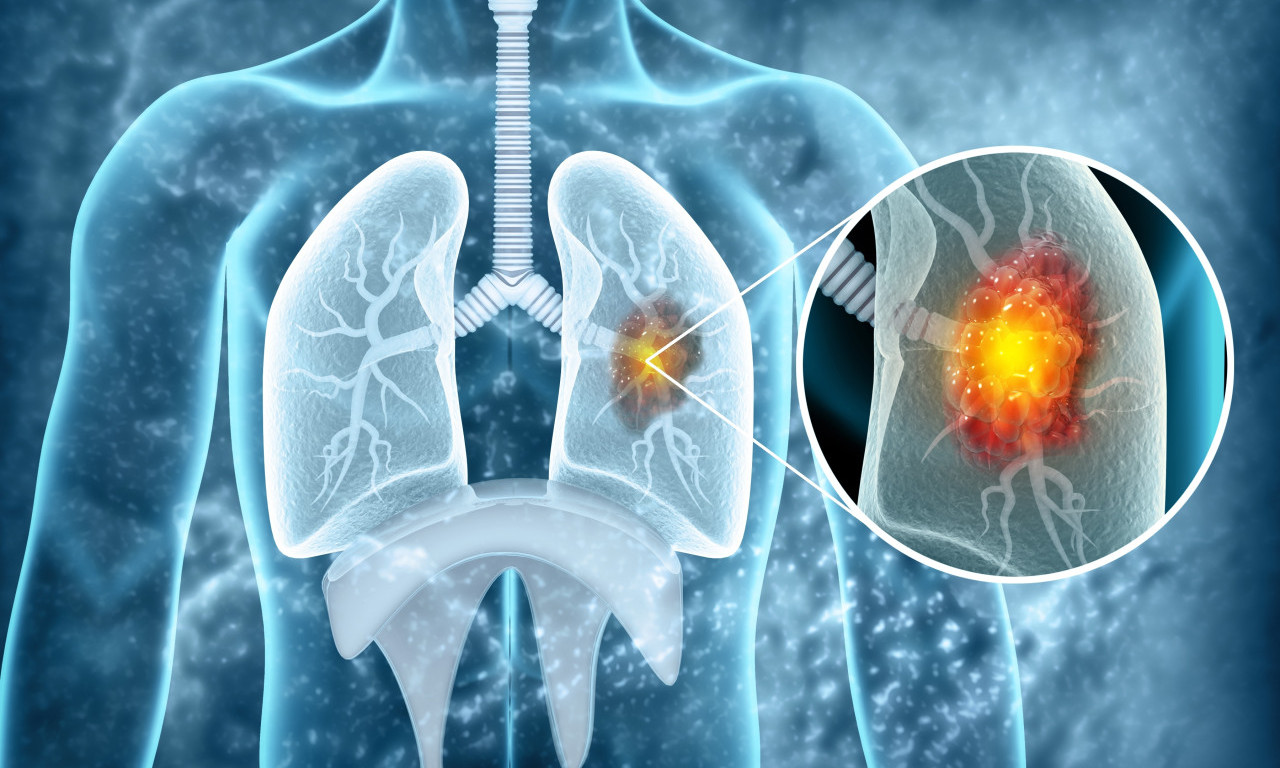

rak pluća

VEŠTAČKA INTELIGENCIJA OTKRIVA RAK PLUĆA MESEC DANA UNAPRED! Potrebno je uraditi osnovne medicinske analize

Da li je NOVI LEK rešenje globalnog problema? Lekari objavili da najefikasnije zaustavlja RAK PLUĆA

Rak pluća je vodeći uzrok smrti od raka u svetu, a godišnje ima 1,8 miliona smrtnih slučajeva od kancera pluća

CRNA STATISTIKA: 70% obolelih RAK PLUĆA otkrije tek kad su ŠANSE ZA IZLEČENJE MINIMALNE, ovo je NAJVEĆI PROBLEM

Doktor je objasnio koje metode lečenja postoje u Srbiji i na koji način se određuje da li će pacijent biti podvrgnut inovativnom lečenju